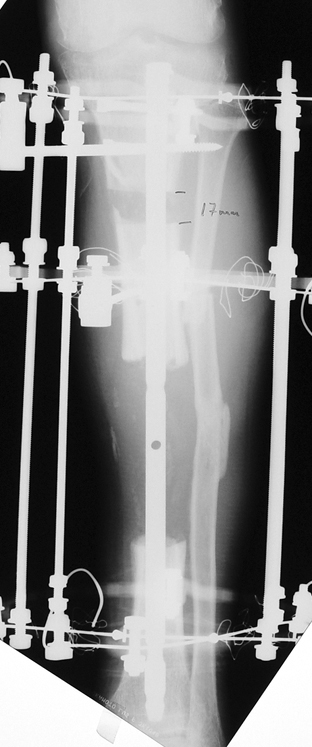

Appropriate radical debridement necessitates excision of all necrotic bone and soft tissues, and frequently causes instability at the involved extremity. The remaining bone and soft tissue defect has to be fixed and reconstructed. The distraction osteogenesis method of Ilizarov is used successfully for achievement of union, correction of the deformity, elimination of limb length inequality and reconstruction of segmental bone defects.

The duration of external fixation (external fixation index) depends on the amount of distraction required, and the extremity is prone to complications during this period. After the distraction phase is completed, the external fixator remains in place during the consolidation phase, which lasts twice as long as the distraction phase; but this period is hardly tolerated. If the external fixator is removed before sufficient consolidation is achieved, fractures, deformity and shortness will be the result. In our department, ‘lenghthening over nail’ method is used in order to decrease the external fixation index and increase patient comfort and activity level. In this method, the intramedullary nail is statically locked after the completion of the distraction phase, and external fixator is removed. The extremity is stabilized by the intramedullary nail during consolidation phase. In this way, complications due to long external fixation index or early removal of the external fixator are avoided.

Case 3